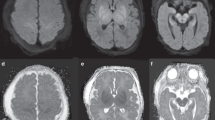

Hypoxic ischemia is a common cause of damage to the fetal and neonatal brain. Although systemic and cerebrovascular physiologic factors play an important role in the initial phases of hypoxic-ischemic injuries, the intrinsic vulnerability of specific cell types and systems in the developing brain may be more important in determining the final pattern of damage and functional disability. Excitotoxicity, a term applied to the death of neurons and certain other cells caused by overstimulation of excitatory, mainly glutamate, neurotransmitter receptors, plays a critical role in these processes. Selected neuronal circuits as well as certain populations of glia such as immature periventricular oligodendroglia may die from excitotoxicity triggered by hypoxic ischemia. These patterns of neuropathologic vulnerability are associated with clinical syndromes of neurologic disability such as the extrapyramidal and spastic diplegia forms of cerebral palsy. The cascade of biochemical and histopathologic events triggered by hypoxic ischemia can extend for days to weeks after the insult is triggered, creating the potential for therapeutic interventions.

Rivkin MJ 1997 Hypoxic-ischemic brain injury in the term newborn: neuropathology, clinical aspects, and neuroimaging. Clin Perinatol 24: 607–626

Menkes JH, Curran J 1994 Clinical and MR correlates in children with extrapyramidal cerebral palsy. AJNR Am J Neuroradiol 15: 451–457

Barkovich AJ, Westmark K, Partridge C, Sola A, Ferriero DM 1995 Perinatal asphyxia: MR findings in the first 10 days. AJNR Am J Neuroradiol 16: 427–438

Hoon AH, Reinhardt EM, Kelley RI, Breiter SN, Morton DH, Naidu S, Johnston MV 1997 Brain MRI in suspected extrapyramidal cerebral palsy: observations in distinguishing genetic-metabolic from acquired causes. J Pediatr 131: 240–245

Roland EH, Poskitt K, Rodriguez E, Lupton BA, Hill A 1998 Perinatal hypoxic-ischemic thalamic injury: clinical features and neuroimaging. Ann Neurol 44: 161–166

Pasternak JF, Gorey MT 1998 The syndrome of near-total intrauterine asphyxia in the term infant. Pediatr Neurol 18: 391–398

Maller AI, Hankins LL, Yeakley JW, Butler IJ 1998 Rolandic-type cerebral palsy in children as a pattern of hypoxic-ischemic injury in the full-term neonate. J Child Neurol 13: 313–321

Rutherford MA, Pennock JM, Counsell SJ, Mercuir E, Cowan FM, Dubowitz LMS, Edwards AD 1998 Abnormal magnetic resonance signal in the internal capsule predicts poor neurodevelopmental outcome in infants with hypoxic-ischemic encephalopathy. Pediatrics 102: 323–328